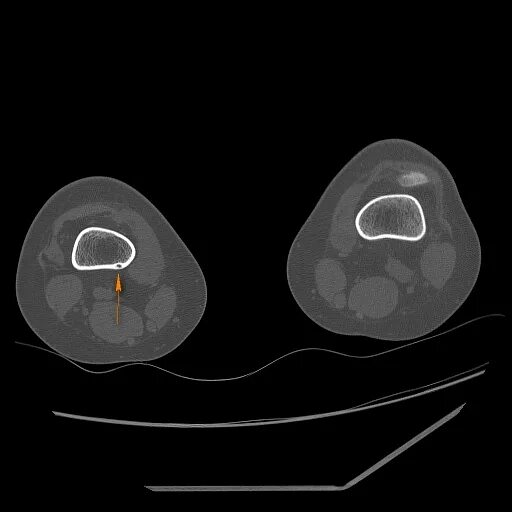

Фиброма кт